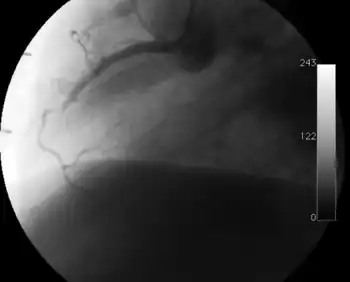

Surveillance is performed by regularly repeating coronary angiography in the cardiac catheterization laboratory, the diagnostic test of choice.[2] This is typically performed annually for the first five years after transplantation.[8] Angiography in CAV characteristically demonstrates diffuse stenoses in large coronary arteries and a reduced number of smaller coronary arteries, also known as "peripheral pruning".[2][6] However, because CAV frequently affects the entire length of the coronary artery, CAV may not be apparent by angiography alone.[2]

Occlusion of the right coronary artery 2 years after heart transplantation.

Partial occlusion of the left anterior descending artery on routine follow-up 8 months after transplantation.